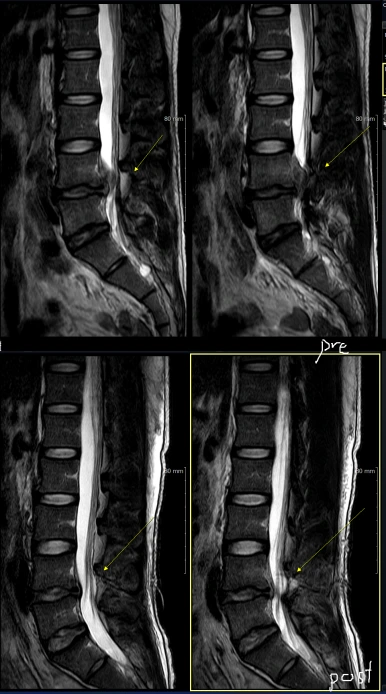

설명드리고 이어서 진행한 MRI 영상을 보니 터져나온 디스크 양이 굉장히 많습니다.

위에 사진 5장은 수술 전, 아래 5장은 수술 후입니다.

내시경으로 보면서 수술 깔끔하게 진행되었고, 디스크는 거의 다 제거되었습니다.

디스크가 up migrated 되어있어서 뼈를 많이 갈아낼 수도 있다고 생각되었는데 (hemilaminectomy 가능성) 지난번처럼 30도 내시경 덕분에 손상부위 거의 없이 안전하게 수술 진행됐습니다.

MRI 좌측 axial 영상 보시면 facet이 거의 온전히 보전된걸 볼 수 있습니다.